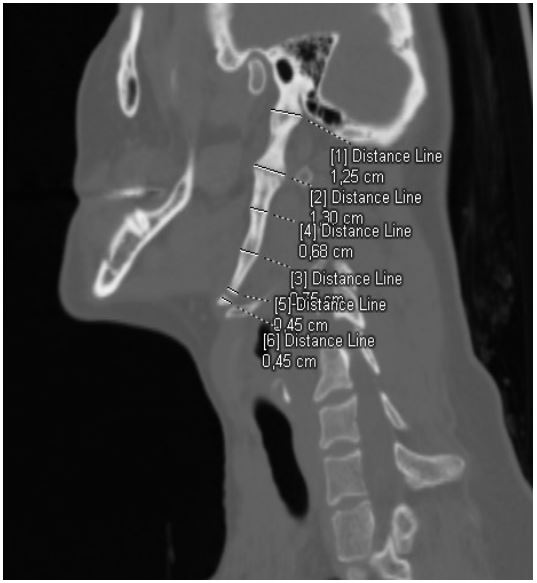

Computed tomography of the neck without contrast administration showed bilateral elongated styloid processes. On the left side the overal lenght of the styloid process was 8,3 cm. Aditionally within the left styloid process we observed two false joints, one of them in the down part, reposition the hyoid bone in caudal direction (Figure 3). Maximum width of the left styloid process was 1,3 cm and it was located at the level of upper false joint. Right styloid process was elongated insignificantly (3,65 cm) and didn’t cause pain or any other symptoms.

Figure 4: Multidetector computer tomography (MDTC) with multi-planar reconstructions (MPR) - left-sided sagittal view. Measurements of the width of left styloid process.